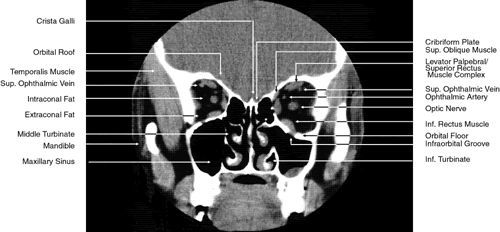

The globe is shown in Figure 12. The orbit and periorbital structures are shown in Figures 13 through 16, and the optic canal is shown in Figures 17 through 26. The cavernous sinus and optic chiasm are shown in Figures 27 and 28, and the posterior visual pathway and cranial nerves are shown in Figures 29 through 33.

Fig. 19. Coronal images through midorbit posterior to the globe. A. Computed tomography scan.B. T1-weighted magnetic resonance imaging.

Fig. 20. Coronal images through orbital apex. A. Computed tomography scan. B. T1-weighted magnetic resonance imaging. C. Anatomic section of a cadaver head at the level of the orbital apex.